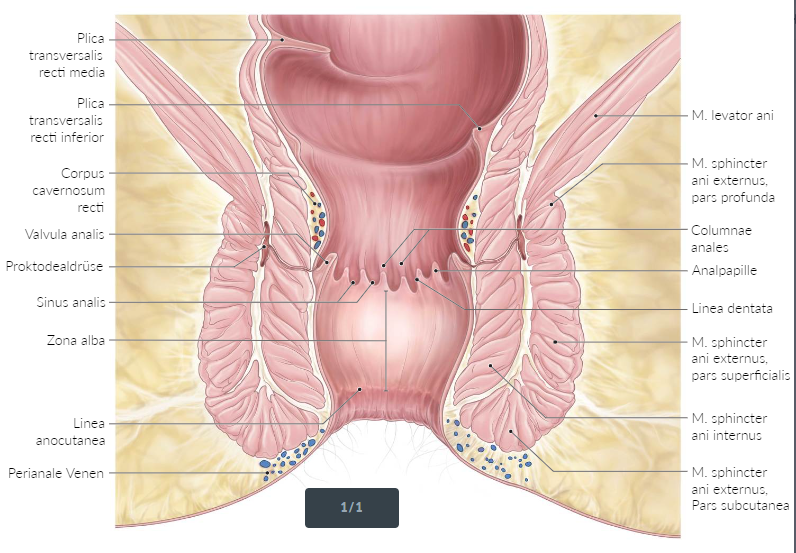

P - Anatomie des Analskanals und Gefäße

A

3-4cm lang

Schleimhaut ausgekleidete Lumen des anus

Obergrenze: Junctio anoretalis/Liena anorectalis (schitbare Schleimhaut)

Untergrenze: Linea anocutanea

Funktion: Kontinenzorgan

Kontinenz mittels M. spinchter anus INTERNUS und EXTERNUS

-> Ersten 2/3 = Coluna analis/Zona colunaris

Krypten/Kryptosen Schleimhaut mit Drüsen

Diese Teil enthalt auch das Corpus Cavernosus mit dem Hämorrhoidalplexus

-> Untere Drittel = Zona Alba

Obergrenze: Linea Dentata

—— Linea Anorectalis—–

Name: ZONA COLUNARIS

2/3 der Kanalanal

Entstehen Kryptens und Analdrüse

Enthalt: Columna Anales = 8-10 Mukosa Schichte

In der Submukosa der Columna Analis findet die Corpus Cavernosus sich

Corpus Cavernosus ist unmittelbal kranial nach Linea Dentata. Da entsteht die Corpus Cavernosus = Plexus Hemorrhoidarius

M. Canalis Analis: Kontrolierte die Spannung und Blutfluss des Corpus Cavernosus

Diese Zone kontrolliert auch die Kontinenz

Analkrypten = Sinus analis, die die Coluna analis trennen

Erkrankung: “innere Hämorrhoiden”

Blutversogung: A. rectalis superior (Ast der A. mesenterica inferior)

Venöseversogung: Abfluss in das Portalsystem

Plexus haemorrhoidalis internus → V. rectalis superior → V. mesenterica inferior

Innervation:

Nn. splanchnici pelvici und Plexus hypogastricus inferior.

——Linea Dentata——-

ZONA ALBA

3/3 = Untere Drittel der Analkanal (1cm)

Ganz feste und viele Verwachsungen mit der Unterlage. Die sinde weisse. Deswegen Zona ““Alba””

Blutversogung: A. rectalis media (Ast der A. iliaca interna)

A. rectalis inferior (Ast der A. pudenda interna)

Venöseversogung:

Abfluss in die systemischen Venen (V. cava inferior)

Plexus haemorrhoidalis externus → V. rectalis media und inferior → V. pudenda interna → V. iliaca interna

Innervation: N. pudendus.

——-Linea anocutanea________

ZONA CUTANEA

Perianale Venen

Erkrankung = Aussere Hämorrhoiden

——-Perianalhaut——

FIM

Extra:

Arterielle Blutversorgung

Oberhalb der Linea dentata (Rektum und oberer Analkanal):

A. rectalis superior (Ast der A. mesenterica inferior)

Unterhalb der Linea dentata:

A. rectalis media (Ast der A. iliaca interna)

Venöser Abfluss

Auf Höhe der Linea dentata befindet sich eine portosystemische Anastomose.

Oberhalb der Linea dentata:

Abfluss in das Portalsystem

How well did you know this?